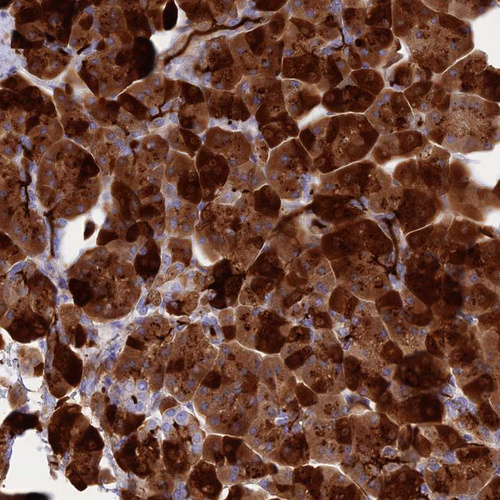

Immunohistochemical staining of human pancreas shows strong cytoplasmic positivity in exocrine glandular cells.